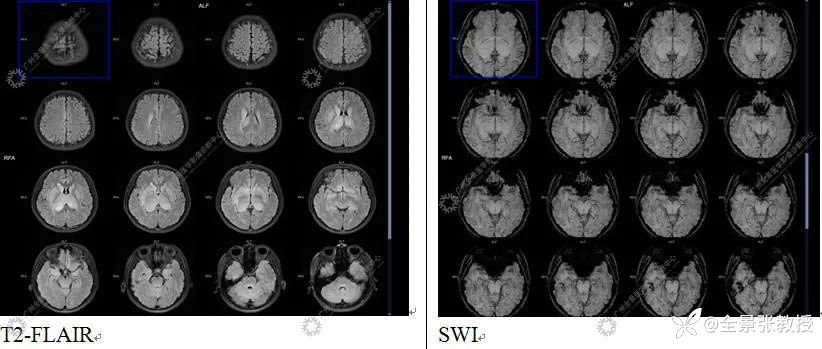

显示:双侧尾状核头-体部、双侧豆状核、双侧丘脑-漏斗-垂体柄、双侧颞叶海马-海马旁回可见对称性异常信号,T1WI呈稍低信号,T2WI及T2W-FLAIR呈稍高信号,DWI大部分呈等信号,右侧丘脑见小片状弥散轻度受限区,SWI未见出血信号;双侧丘脑肿胀,体积增大;MR波谱成像示双侧背侧丘脑NAA峰明显减低,Cho峰升高;双侧尾状核、豆状核各峰尚可,上述部位MR灌注减低,相应脑区FDG摄取对称性弥漫性减低,SUVave为2.92,其中右侧丘脑后缘见小条片状FDG摄取稍高,SUVmax为6.23。

诊断结果为:双侧尾状核头-体部、双侧豆状核、双侧丘脑-漏斗-垂体柄、双侧颞叶海马-海马旁回对称性异常信号,且MRI灌注及糖代谢弥漫性明显减低,提示局部脑功能受损明显;双侧丘脑肿胀;颅脑MRI波谱示病变区NAA峰明显减低,Cho峰升高,提示相应部位神经元受损;考虑中枢系统恶性肿瘤,弥漫性中线胶质瘤可能。后病理证实为H3K27M突变型弥漫性中线胶质瘤。